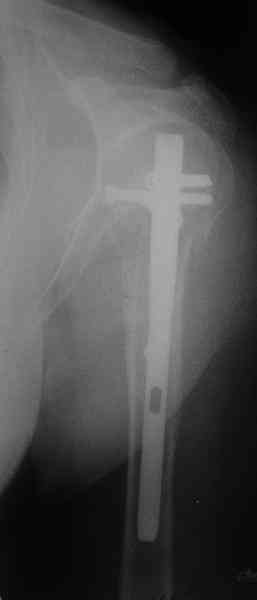

Another option could be closed nailing, see an example, the surgery was done 2 days ago. In common such surgeries are performed under regional anesthesia, not general.